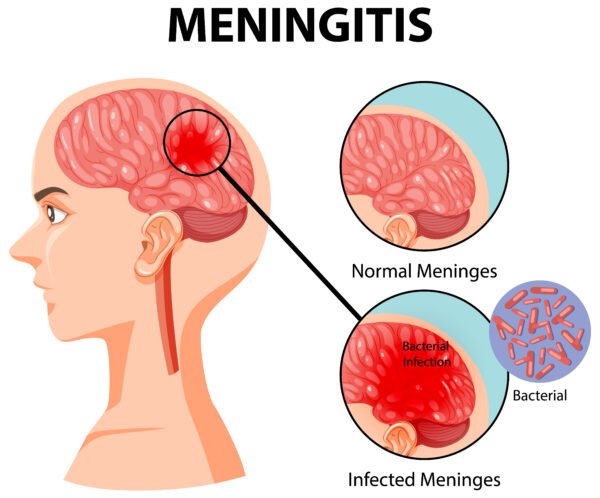

- Meningitis